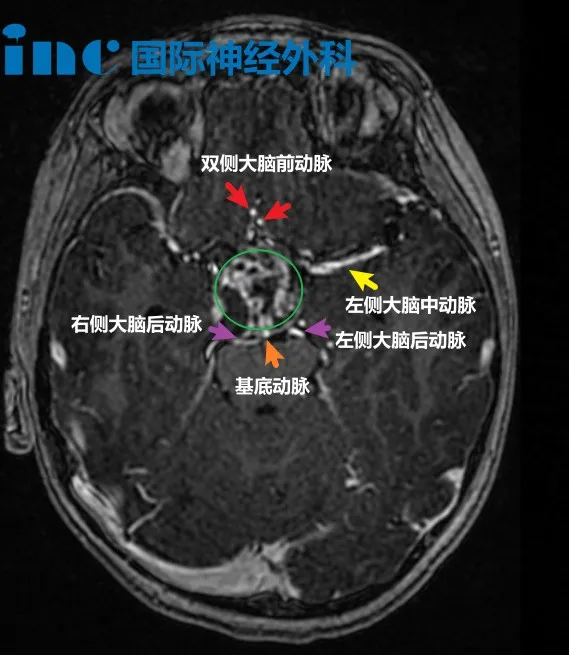

▼鞍区肿瘤,颅咽管瘤,和周围大血管动脉关系紧密